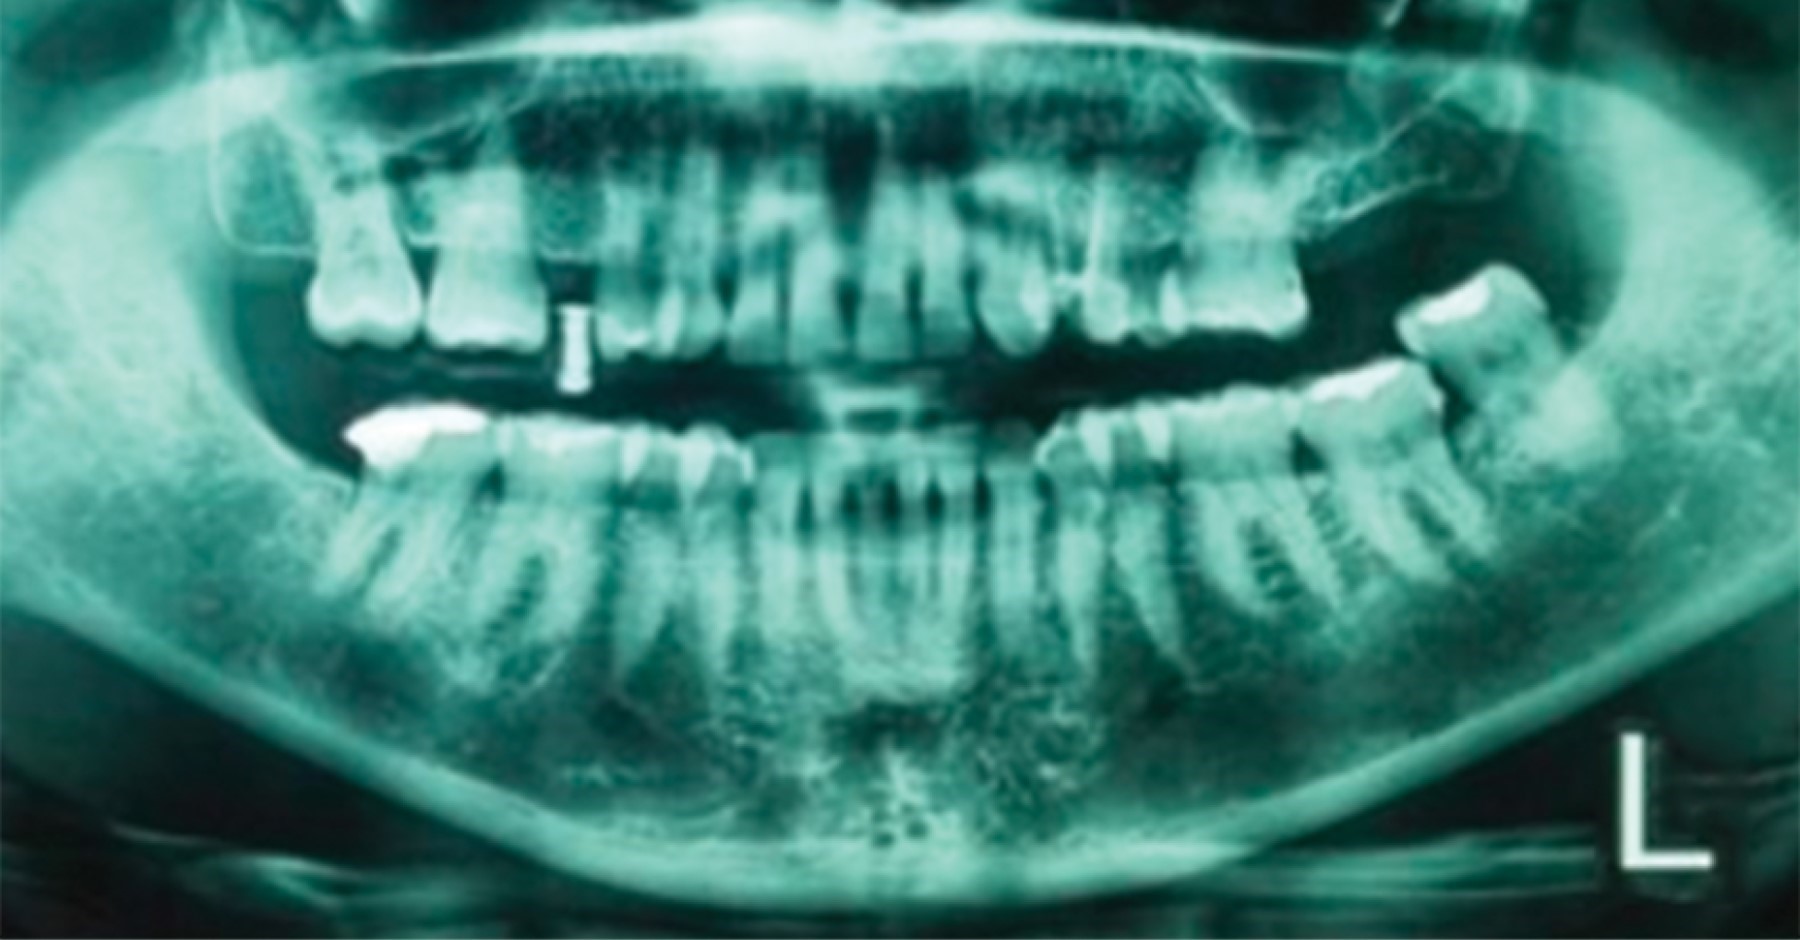

Placement Of Implants In A Patient With A History Of Bisphosphonates Taken

Placement Of Implants In A Patient With A History Of Bisphosphonates Taken